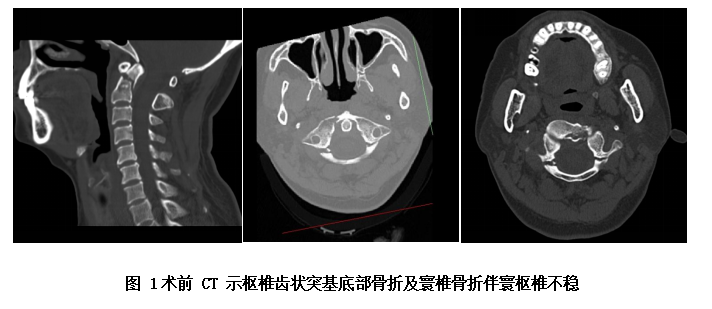

医院骨伤科上肢脊柱专业组组长周中伦副主任医师及上肢脊柱组陈仕文主诊医师,十分关注杨阿姨的病情,在她入院后立即给予其激素稳定神经细胞膜及脱水治疗,同时予以头颈部制动牵引。在完善相关检查后,学科带头人刘志勇主任医师组织骨伤科脊柱专业医生团队讨论杨女士的病情,诊断她的伤病为“寰椎前后弓骨折(GehweilerⅢa)、齿状突骨折(AndersonⅡb)、寰枢关节脱位”。枢椎齿状突骨折及寰椎骨折是颈椎外伤中的一种严重损伤,如果处理不当会导致寰枢椎不稳定、半脱位甚至脱位,压迫延髓,造成高位脊髓损伤,甚至危及生命。

若采用手术方式有利有弊,好处是手术成功后,患者就能较快恢复,及时解决患者的病痛,同时还能避免患者长期卧床、颅骨牵引的痛苦及骨折不愈合的风险。不利是手术风险较大,患者有可能下不了手术台,因为上颈椎(即寰枢椎)手术为脊柱骨科最高风险手术之一,被称为脊柱外科手术上的明珠。因颈部后方显露位置深在,椎管内为延髓,椎弓旁边有椎动脉,任何操作失误都将造成严重后果甚至危及生命,同时该类手术对麻醉、体位及手术操作都有特高的要求。且通过CT片发现,患者还存在椎动脉高跨,极大地增加了手术风险及难度。